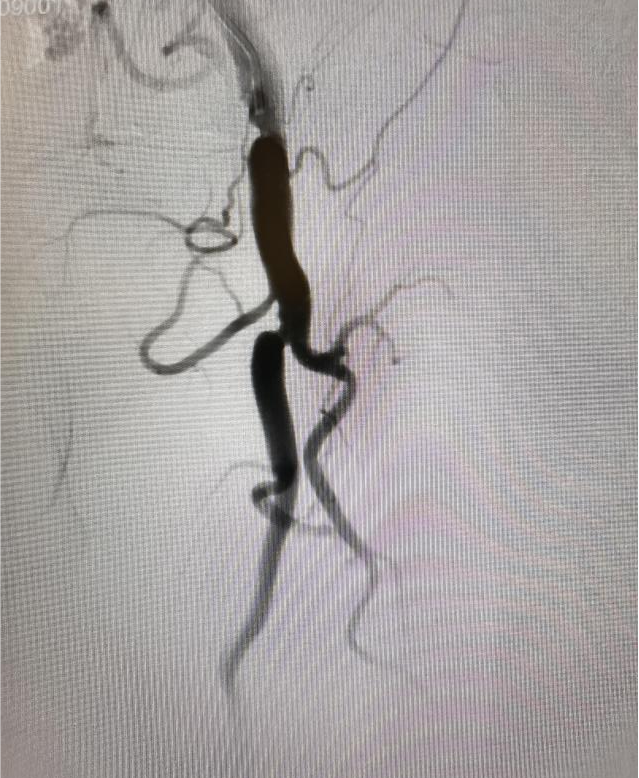

(图2:下肢造影提示左侧股浅动脉闭塞)

面对这一技术挑战,刘超医生提出创新性解决方案:“正向不通,就尝试逆向突破。”在充分术前准备和严密风险评估基础上,手术团队果断采用逆行介入技术:于患者膝关节上方约2厘米处对股浅动脉远端进行精准穿刺,同步从近端与远端双向推进导丝。术中巧妙运用超滑导丝配合强支撑导管,实施“双向穿针引线”策略,最终成功实现导丝在闭塞段内的精准“会师”,逐步打通顽固性阻塞,恢复下肢动脉血流。术后患者下肢灌注明显改善,双下肢无力症状显著缓解,恢复情况良好,目前已可逐步开展康复训练。